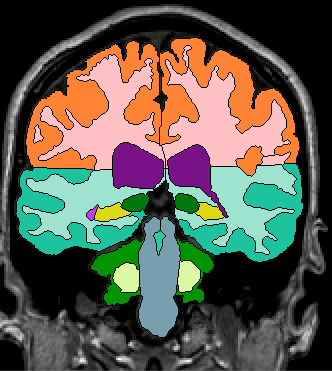

Because proper segmentation of the cerebral exterior includes a clearly drawn in Sylvian Fissure, segmentation of the insula in the more posterior coronal slices is simply a matter of “extending” these drawn in lines to the medial white matter (Fig 4-5)

Figure 4                  Figure

5